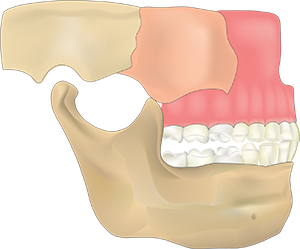

3D CT을 통해 얻은 데이터로

뼈의 상태와 신경관의 위치를 파악하고

가상 모의 수술을 진행하여

식립위치를 정확도 높게 파악합니다.